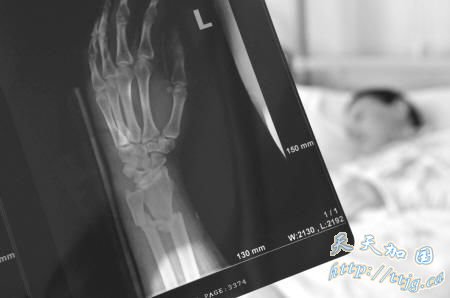

妻子手上多处骨折

施维意的妻子吴文妹仍躺在古田县医院病床上,神志仍有些不清醒。一个月过去了,额头上留下深深一道伤痕,左手仍裹着厚厚的纱布。

据古田县医院主治医生施医生介绍,吴文妹头上有六道刀伤,每条长六七公分,深及颅骨;左手腕尺骨和桡骨粉碎性骨折,右手第五掌骨骨折,均被棍棒击伤。